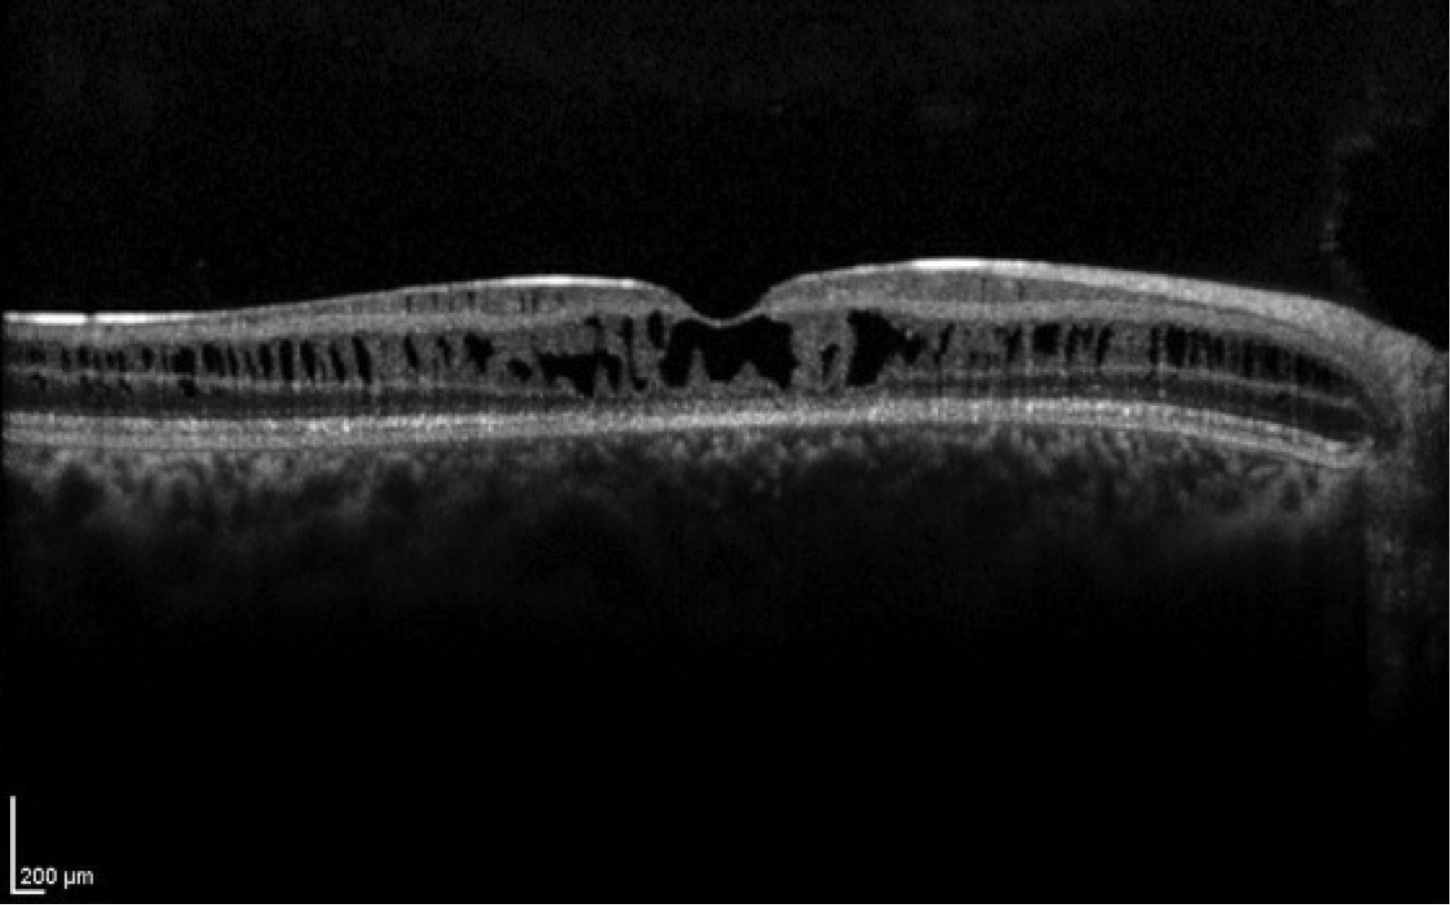

Case 14 is an 11 year old male with 20/60 vision. His parents have normal vision but he has a brother with reduced acuity. Fundus examination reveals normal disks and vessels, but there is a stellate arrangement of cysts centered on the fovea.

Optical coherence tomogram of the right eye.